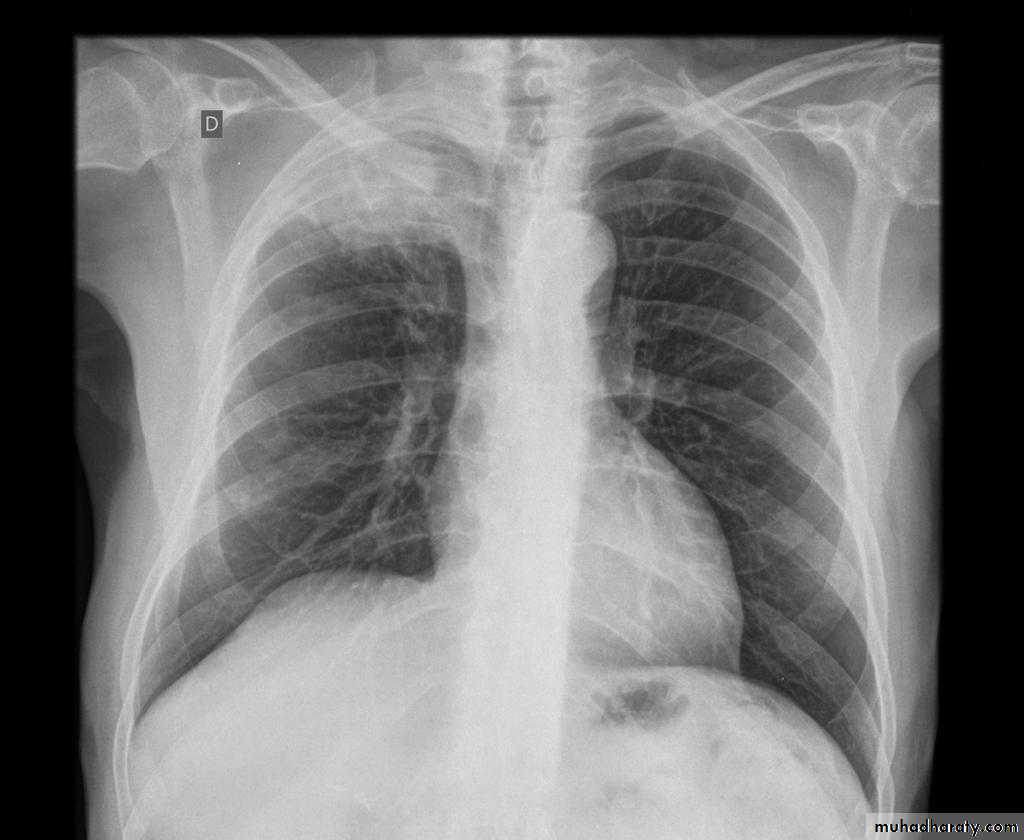

Plain radiograph

Chest x-rays are usually abnormal

1. Tram-track opacities are seen in cylindrical bronchiectasis, and

2. air-fluid levels may be seen in cystic bronchiectasis.

Honey comb shadow

3.Overall there appears to be an increase in bronchovascular markings, and bronchi seen end on may appear as ring shadows .

4.Pulmonary vasculature appears ill-defined, thought to represent peri bronchovascular fibrosis .